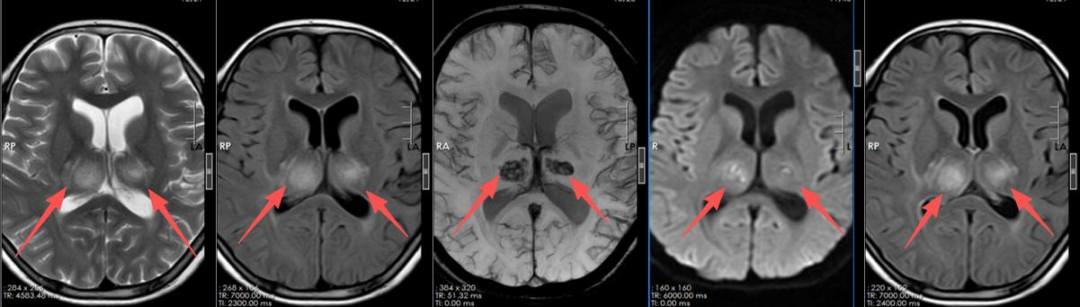

“入院时,立即转入了重症医学科。”该院神经内一科副主任匡祖颖接诊后,完善MR检查后发现患儿脑干、双侧丘脑、双侧基底节、右侧小脑、双侧顶叶区部分脑沟多发病灶,最终诊断患儿是急性坏死性脑病。

入院时影像显示多发病灶